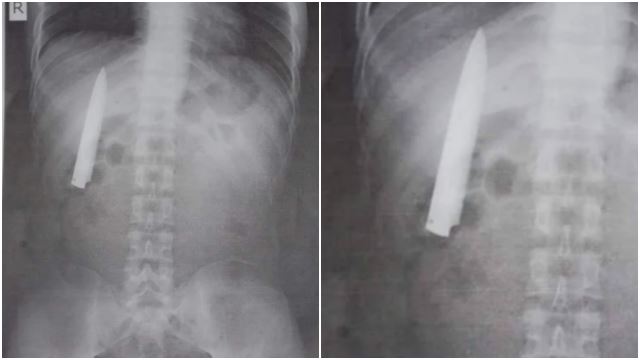

Selalu Sakit Dada, Lelaki Tak Sangka Ada Pisau 4 Inci Dalam Badan